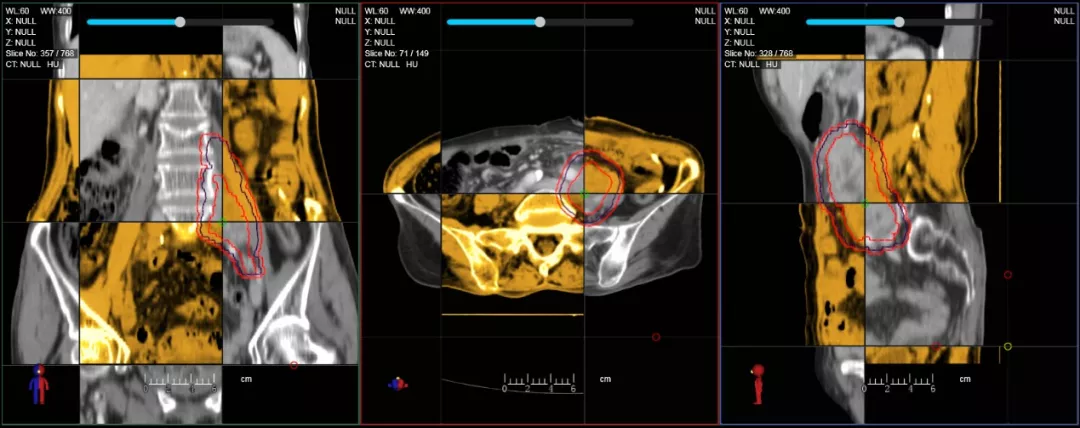

CT-IGRT配準(zhǔn),除骨性標(biāo)記外,還能以器官、軟組織等作為參考,真正找到配準(zhǔn)目標(biāo)

一體化CT-linac讓自適應(yīng)放療ART概念變?yōu)楝F(xiàn)實(shí)。患者全療程狀態(tài)監(jiān)控,適時(shí)在線調(diào)整治療計(jì)劃,精準(zhǔn)控制治療劑量,為患者動(dòng)態(tài)定制個(gè)體化治療方案。uAI賦能智能勾畫(huà)和自動(dòng)計(jì)劃,秒級(jí)勾勒靶區(qū)和危及器官,大幅縮短自適應(yīng)放療時(shí)間。